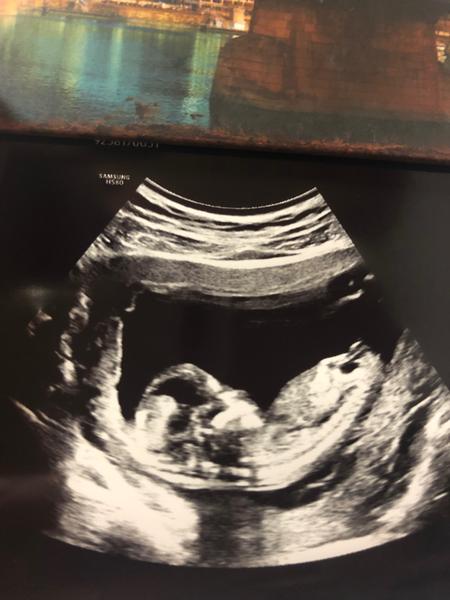

Na tehle fotce je dite pateri k utz, takze pohlavni hrbolek neni vubec videt. Neni mozne podle tehle fotky rict, bohuzel.

@mamikry Jenze lekari nevidi pouze fotku. Lekari vidi hybajici se utz, kde maji pohled i na dite primo z boku, kde se to da poznat. A nejde o odhad, ale o presne urceni. Ale z fotky to proste odhadnout nejde - tam to bud videt jednoznacne je, nebo (jako u teto fotky) vubec neni. To, ze mate za sebou smutne dny vysvetluje, ze si to berete tak osobne. Ja jsem proste chtela opravit, co jste napsala, aby si autorka nedelala na nejake pohlavi "nadeji" a nebyla pak treba zklamana nebo i neco nekoupila, i kdyz jde jen o diskuzi.

@krupka3 taky jsem netušila, že by to z toho třeba nebylo poznat. Měla jsem za to že tam pohlavní hrbolek je🙂 přeci jen je to můj první potomek tak vím o tom prdlačku . Jen jsem to zkusila sem hodit zajímalo mě kdo co řekne a kdo se trefí. Z pohlaví zklamaná nebudu, protože mi to je jedno chci hlavně zdravého potomka. Jen jsem zvědavá a napnutá tak proto z toho dělám tyhle hádanky a zkoumám to doma 😃 věci nakupuji neutral a až mi potrvdí lékař pohlaví začnu s nákupem pořádným. Rozhodně bych tady nerada vyvolávala nepříjemné diskuze přeci jen od toho to tady není. Bohužel setkávám se s tím tady často.

Nejraději bych celý příspěvek smazala když je tam stejné prd vidět tedy... ale neumim to😀